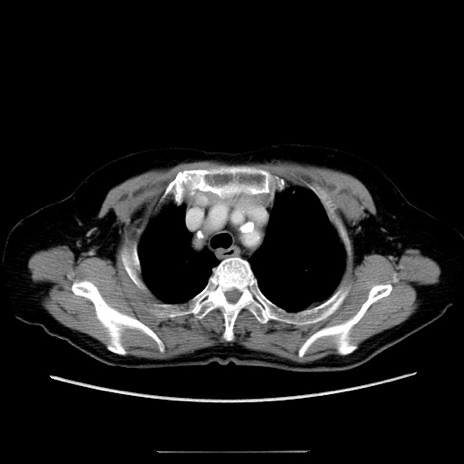

症例5(横断像)

【症例】70歳代女性

【主訴】お腹が張る

【現病歴】1週間くらい前から腹部膨満の自覚あり。昨日夜から増悪したため、本日救急外来受診。

【身体所見】意識清明、BT 36.5℃、BP 165/106mmHg、HR 80bpm、SpO2 98%、腹部:膨満、軟、自発痛・圧痛なし、触診にて不快感あり、腸蠕動音:減弱

【データ】WBC 12600、CRP 1.04